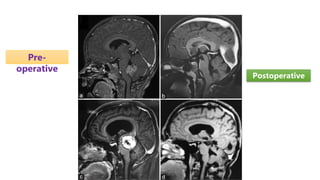

Pre-

operative

Postoperative

Preoperative

• Preoperative stereotactic imaging to guide the surgical approach in order to

minimize manipulation of normal tissue and maximize tumor resection

• Intraoperative MRI imaging, including functional MRI to aid in intraoperative

decision making

• Postoperative imaging, preferably by MRI, is performed within the first 24 to

72 hours